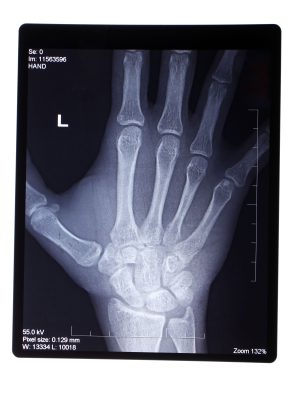

As imagens radiográficas tiveram sua descoberta em 08 de Novembro de 1895, quando o pai da radiologia, o físico alemão Wilhelm Conrad Roetgen, viu sua mão sendo projetada numa tela enquanto trabalhava com radiações.

Após essa observação, imaginou que de um tubo em que ele trabalhava deveria estar sendo emitido um tipo especial de onda que tinha a capacidade de atravessar o corpo humano.

Naquela época esta descoberta revolucionou a medicina, pois havia se tornado possível a visão do interior dos pacientes e ao passar dos anos, este método evoluiu e assumiu uma abrangência universal na pesquisa diagnóstica do ser humano.

Na odontologia essa especialidade que examina os dentes e a face de uma pessoa, é considerada uma ferramenta essencial de diagnóstico e interpretação. Já que permite o estudo de toda a arcada dentária.

A radiologia odontológica pode ser um exame 0intraoral e extraoral, realizados por dentro e fora da boca, respectivamente. Com as radiografias, um cirurgião-dentista pode analisar possíveis complicações, mas nem sempre promove um diagnóstico conclusivo.